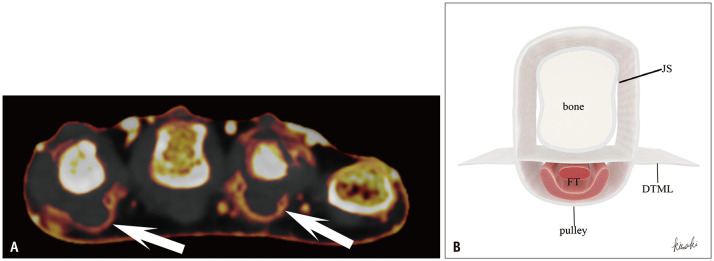

Fig. 11. Extensor peritendinitis at various joint levels in psoriatic arthritis on dual-energy CT iodine maps. A: Sagittal image of the finger in a 42-year-old male shows swelling and enhancement around the extensor tendon slightly proximal to the metacarpophalangeal joint (arrow). B: Sagittal image of the finger in a 34-year-old female shows swelling and enhancement around the extensor tendon at the proximal interphalangeal joint (arrow). C: Sagittal image of the finger in a 45-year-old male shows prominent swelling and enhancement around the extensor tendon at the DIP joint. Abnormal enhancement within the DIP joint reflects capsular synovitis (arrow). DIP = distal interphalangeal.

Typical functional enthesitis of the extensor tendon at the MCP joint in PsA appears as swelling and abnormal enhancement slightly proximal to the joint. This occurs because the friction site—between the extensor tendon and the metacarpal bone when the joint is flexed—shifts proximally when the joint is extended (Figs. 10, 11). Although inflammation around the extensor tendon at the MCP joint may not be considered specific for PsA, it may become more specific when extensor peritendinitis occurs at the PIP or DIP joints, where synovial tissue may be absent (Fig. 11).